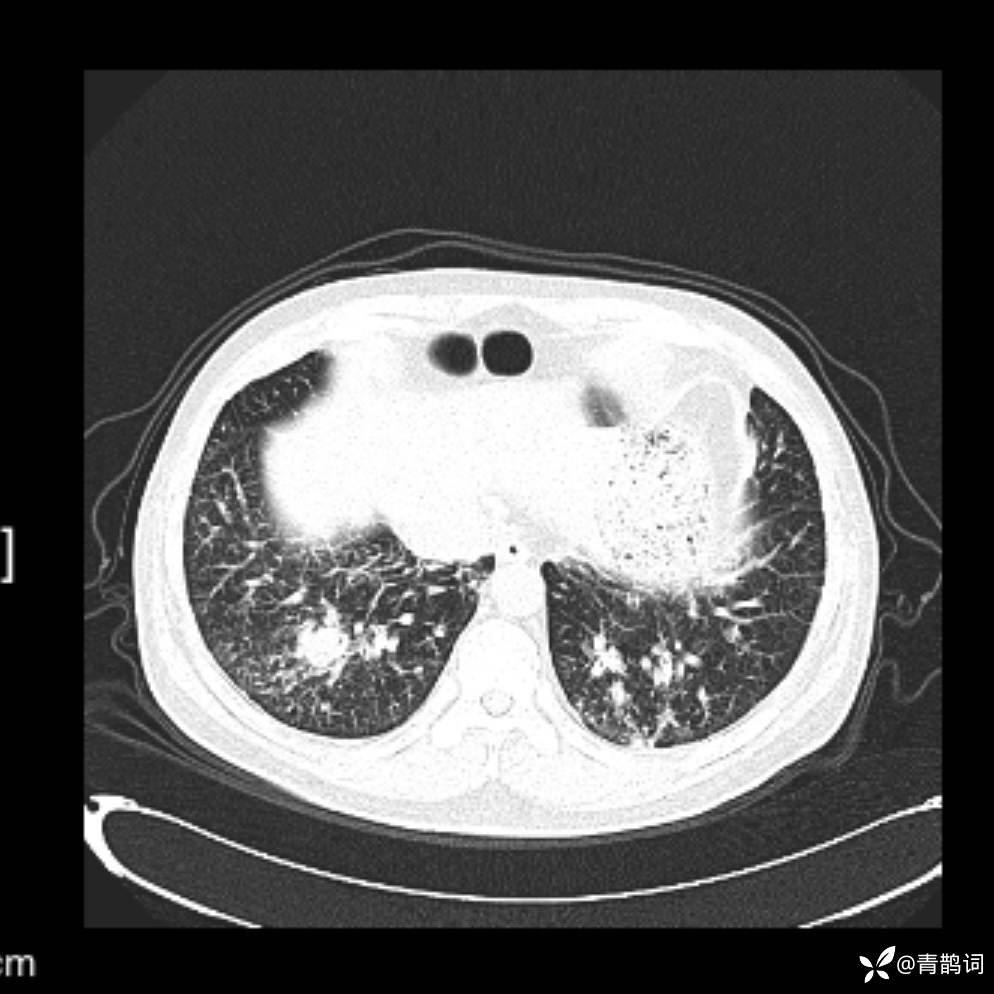

患者年龄:30岁。

患者性别:男。

简要病史:左颜面部肿胀2年,反复咳嗽咳痰,逐渐加重。

辅助检查